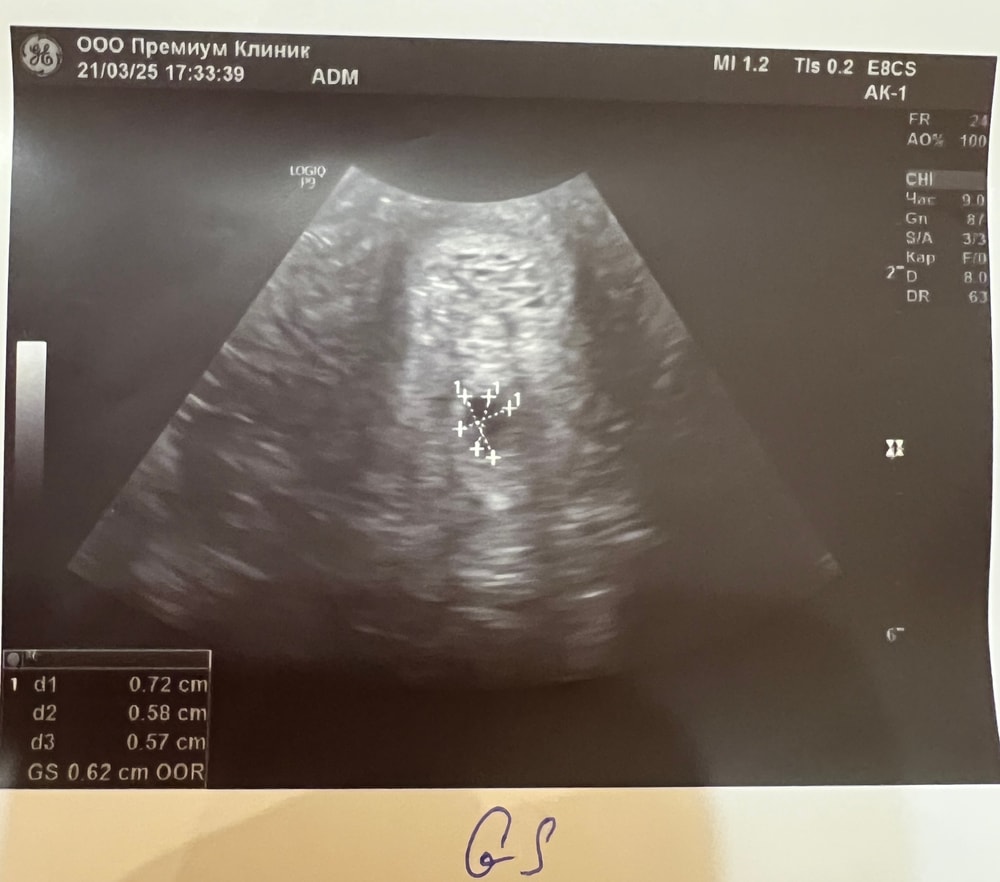

во вторник узи показало ПЯ 3 мм

сегодня показало СВД 6.2 мм, ктр и жм 2,2 мм